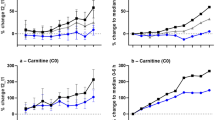

The influence of the pre-autopsy interval was also examined by comparing it against the change in IAA concentrations in the same case. This was assessed in 18, 22, and 9 cases for trans-IAA, cis-IAA, and TIAA, respectively (Fig. 1). The pre-autopsy interval ranged up to approximately 8.5 days with each case plotted in sequence from lowest to highest pre-autopsy interval. The largest ΔConc was approximately 1,000 %, while there were also some cases where concentrations were considerably lower than at mortuary admission. Although there appears to be a slight relationship for AUT concentrations to rise with prolonged collection times, there were also cases where all IAA concentrations decreased, particularly for cases collected between the 3-5 days pre-autopsy interval region.